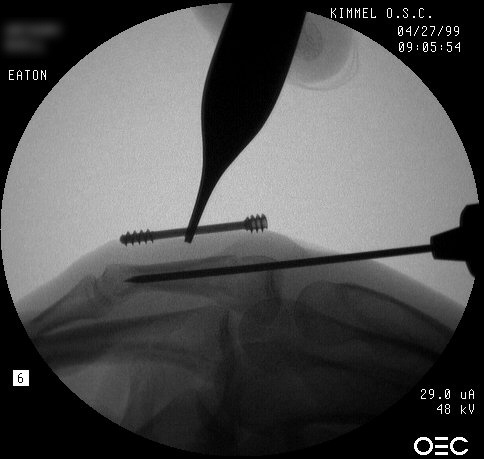

| Proximal phalanx fractures are a common problem with many treatment options. These images illustrate a technique of stabilization using intramedullary Herbert screws placed percutaneously through the base of the proximal phalanx. Provisional fixation is obtained with K wires which are replaced with Herbert screws, which simply follow the soft tissue path of the pin tract to the bone. Self tapping screws are not used in this technique, as the cutting threads catch on soft tissues. |